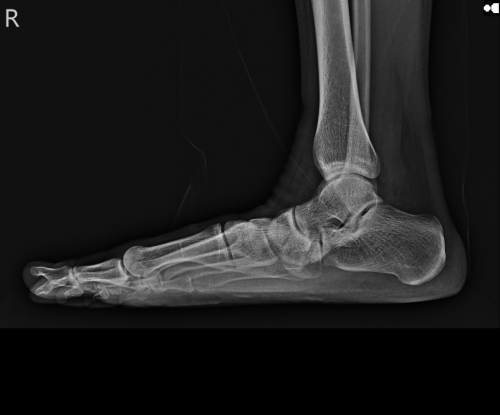

부주상골증후군은 복사뼈 밑 2㎝에 위치한 뼈에 통증이 생기는 질환이다.

‘액세서리 뼈’라고도 불리는 부주상골은 발목과 엄지발가락을 이어주는 주상골 옆에 위치해 어느 정도 식별 가능하다. 이곳에 발생하는 부주상골증후군은 태어날 때 뼈가 정상적으로 유합되지 못해 나타나며 10명 중 1명꼴로 발견된다. 주로 뼈가 발달하는 13~15세 사이 나타나지만 성장통으로 치부하거나 방치하는 경우가 많다. 일상생활에서 크게 불편함이 없지만 농구나 발레, 인라인 스케이트처럼 발에 부담이 심할 운동을 하면 부주상골이 눌려 통증과 부종이 생길 수 있다.

부주상골은 평발과도 관련이 있다. 정강이와 종아리 사이에서 내려온 힘줄(후경골건)은 원래 주상골에 붙어 있어야 하는데 부주상골이 있는 사람은 힘줄이 부주상골에 접해 있다. 이로 인해 부주상골이 계속 손상되면 힘줄이 이탈하면서 발바닥 모양이 평발로 변할 수 있다.

평발을 부르는 부주상골증후군